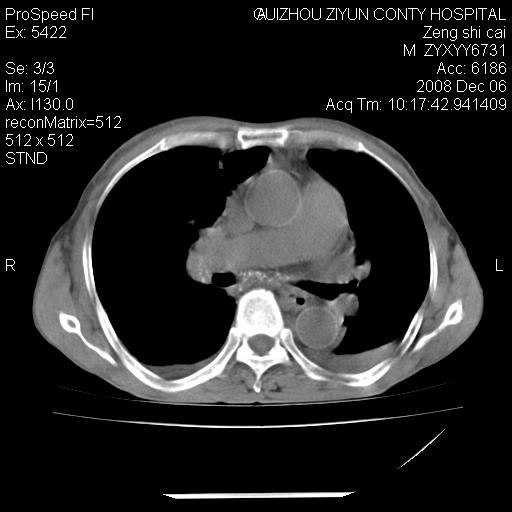

标题: CT16961:M、71岁,咳嗽半年,无血痰;胸片示右肺占位。 [打印本页]

标题: CT16961:M、71岁,咳嗽半年,无血痰;胸片示右肺占位。

右肺癌并纵隔淋巴结及胸膜转移可能性大

右肺癌并纵隔淋巴结及胸膜转移。建议气管镜

右肺纵隔型肺癌伴纵隔淋巴结及胸膜转移!

右肺纵隔型肺癌伴纵隔淋巴结转移!双侧胸水!

1)考虑右肺上叶纵隔型肺癌伴纵隔淋巴结转移。2)心包积液,双侧胸腔积液。

右肺癌并纵隔淋巴转移,腹膜后转移可能性大,两侧胸腔积液

右肺上叶纵隔型肺癌伴纵隔淋巴结转移。心包积液,双侧胸腔积液。

右上肺癌并纵隔淋巴结及胸膜转移。

建议强化!主要鉴别是淋巴瘤与肺癌淋巴结转移。

右肺纵隔型肺癌伴纵隔淋巴结及胸膜转移